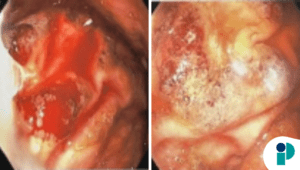

El diagnóstico de la colitis ulcerosa se realiza a través de un examen físico completo, análisis de sangre, estudios radiológicos y, sobre todo, una colonoscopia. “Durante la colonoscopia, podemos ver directamente el estado del intestino y tomar biopsias para confirmar la inflamación en las capas más profundas del colon”, comentó el especialista. “A través de los marcadores de inflamación como el C-RP y la tasa de sedimentación, podemos identificar posibles alteraciones que indican que algo no está funcionando correctamente.”

En relación con el cáncer de colon, una de las complicaciones más graves de la colitis ulcerosa es su asociación con un mayor riesgo de desarrollar este tipo de cáncer. “La inflamación crónica y constante en el colon aumenta significativamente el riesgo de mutaciones celulares, lo que puede derivar en cáncer”, explicó el Dr. Manfredo.

“Por ello, es crucial que los pacientes con colitis ulcerosa se sometan a colonoscopias regulares, al menos cada dos años, para detectar cambios precoces que puedan indicar la presencia de displasia, una alteración precursora del cáncer”, señaló el experto.